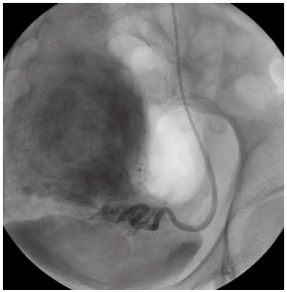

Эмболизация маточных артерий (ЭМА) — способ лечения миомы матки без хирургической операции. Эффект достигается за счет перекрытия кровотока в узлах миомы с помощью специального препарата, который вводится в артерии матки по тонкой трубке (катетеру) через бедро. Препарат содержит мелкие шарики (эмболы), которые перекрывают артерии миомы, после чего она погибает в течение нескольких часов. Эмболизация маточных артерий позволяет во многих случаях отказаться от необходимости удаления матки при миоме и сохранить репродуктивную функцию.

При миоме ЭМА вызывает прекращение кровотока по ветвям маточных артерий, кровоснабжающим миому. Разный диаметр питающих миому ветвей и ветвей, питающих миометрий, приводит к минимальному воздействию на сосуды неизмененного миометрия. После прекращения кровоснабжения мышечные клетки, формирующие миому, гибнут. В течение нескольких недель происходит их замещение соединительной тканью. Затем в процессе «рассасывания» этой ткани происходит значительное уменьшение и/или полное исчезновение узлов, а симптомы миомы проходят.